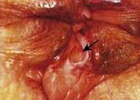

Piles :- This is one of the Painful and awkward issue, It influences huge no of people groups the world over, This infection make individuals less interest in any sort of action. you should accept fundamental treatment for Plies at once, Surbhi Hospital the one of best renowned Piles center in Modasa area settle of aravally.